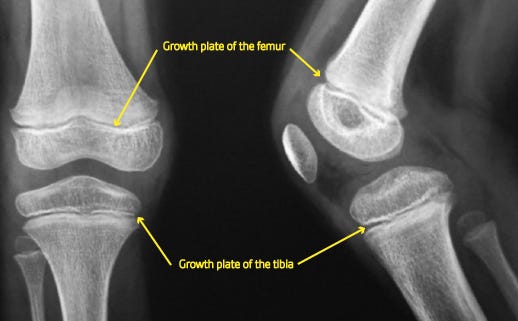

This is part 7 in the series on ACL reconstruction patella tendon autografts. Read part 6 here. The choice of graft for anterior cruciate ligament (ACL) reconstruction should be individualized based on factors such as the athlete's age, activity level, and specific needs. In this section, we will discuss the importance of considering the athlete's speci…